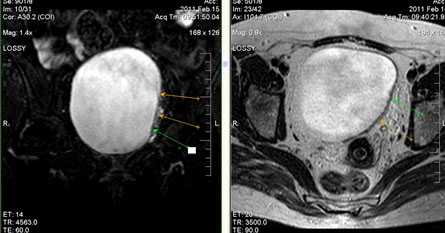

Дивертикулы мочевого пузыря.

Это локальное выпячивание стенки мочевого пузыря. Преобладают у мужчин, частота их встречаемости увеличивается с возрастом.

Развивается дивертикул, как правило, на фоне длительного повышения внутрипузырного давления при инфравезикальной обструкции (доброкачественная гиперплазия, рак предстательной железы, стриктуры уретры). Существует высокий риск развития уротелиального рака в дивертикуле мочевого пузыря за счет задержки в нем канцерогенных веществ.

При больших размерах дивертикулов показано оперативное лечение. По данным МРТ определяется локализация, размеры и осложнения дивертикула (воспаление или развитие опухоли).

а) Т2-сагиттальное изображение б) Т2-аксиальное изображение.

Истончение стенки и увеличения объема мочевого пузыря на фоне хронической инфравезикальной обструкции (вследствие ДГПЖ). Видна трабекулярность стенки мочевого пузыря, дивертикул задней стенки мочевого пузыря слева (б), стрелка; двусторонняя уретерэктазия.